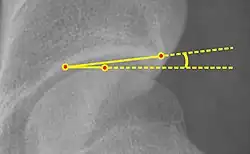

| Alpha angle |  |

Degree of bulging of the femoral head-neck junction: In normal conditions there is a symmetric concave contour at the junction of the femoral head and neck. Loss of this concavity or bone bulging may lead to cam type impingement. The degree of this deformity can be measured by the alpha angle. Although it can be measured in the cross-lateral view, the 45° Dunn view is considered more sensitive and the frog leg view more specific in determining pathologic values. |

|